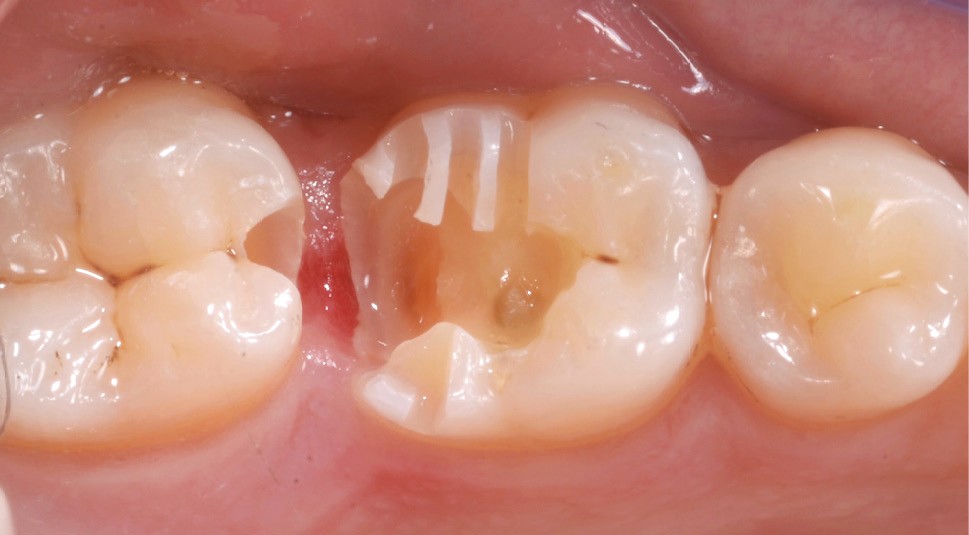

Lors de la préparation d’une cavité pour inlay/onlay, il est fréquent d’être confronté, en fin de nettoyage, à la présence d’une ou plusieurs parois résiduelles dont la résistance mécanique paraît douteuse du fait de leur localisation ou de leur épaisseur. Les parois épaisses (+ de 2 mm) peuvent généralement être conservées (cas clinique 1) et les parois fines (- de 1 mm) doivent généralement être recouvertes. Un inlay (en composite ou en céramique) est alors réalisé. Il doit avoir lui même, au final, une épaisseur globale minimale de 2 mm pour assurer sa résistance mécanique intrinsèque à la mastication. Si un recouvrement cuspidien est indiqué, la réduction occlusale doit donc se faire sur 2 mm de hauteur au minimum [1, 2].

Mais qu’en est-il des parois résiduelles d’épaisseur intermédiaire (entre 1 et 2 mm) (cas clinique 2) ?

Le pronostic clinique semble plus favorable pour les prémolaires que pour les molaires [3-5], car une plus grande résistance est généralement nécessaire pour les parois des molaires. Mais si 75 % des fractures à la mandibule affectent les molaires, et plus particulièrement la première molaire, au maxillaire, les fractures se répartissent équitablement entre le secteur molaire et le secteur prémolaire [6]. L’épaisseur de l’émail, la largeur de la cuspide comme les…